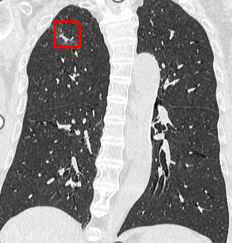

患者陈先生,83 岁,2 年前体检发现双肺多发磨玻璃结节,其中右肺上叶尖段结节在年度随访过程中右肺尖部结节逐渐增大、实变成分逐渐增多。今年 8 月份复查时该结节已经具有空泡征、毛刺征、血管穿行等多个恶性征象,考虑肺癌可能性大,需要积极处理,患者到我院肺结节门诊就医。呼吸内科梁伟权主任综合评估患者全身情况、基础疾病及肺结节位置等情况。